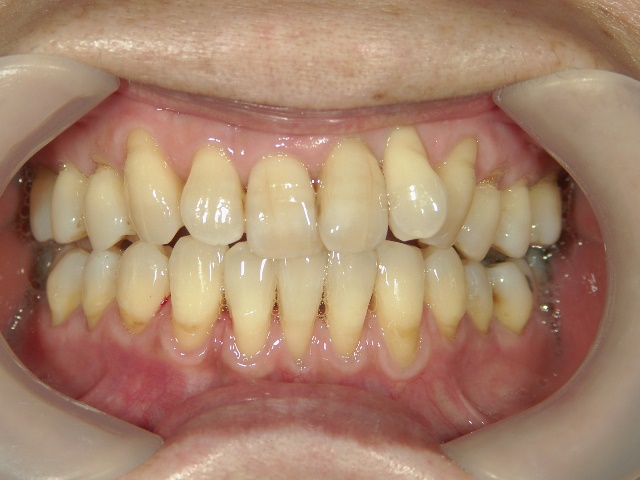

矯正歯科 治療前矯正歯科 治療前

矯正歯科 治療前